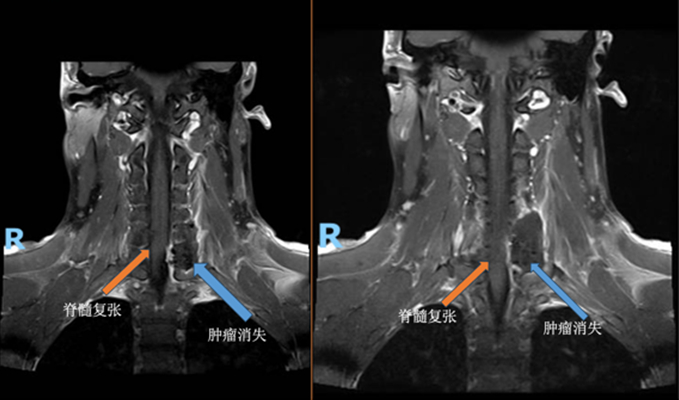

通过该切口入路,在仪器的帮助下精准定位了肿瘤的位置,顺利切除椎管内的小肿瘤以及椎管外的大肿瘤。术后,李哥的椎体稳定性没有受到影响,也无需进行椎骨固定。

据悉,本例手术是深圳第一例脊椎旁正中微创肿瘤切除手术。精巧、微创的手术为患者带来福音的同时,也给深医神经外科带来了全新的椎骨肿瘤切除理念和技术。

此次手术是由天津市环湖医院神经脊柱组组长刘伟教授主刀,深圳市人民医院神经外科主任胡继良及副主任医师罗伟坚协助,仅仅使用一个微创的小切口就一次性全切贯穿椎管内、外的复杂大肿瘤,效果良好,患者顺利康复出院。